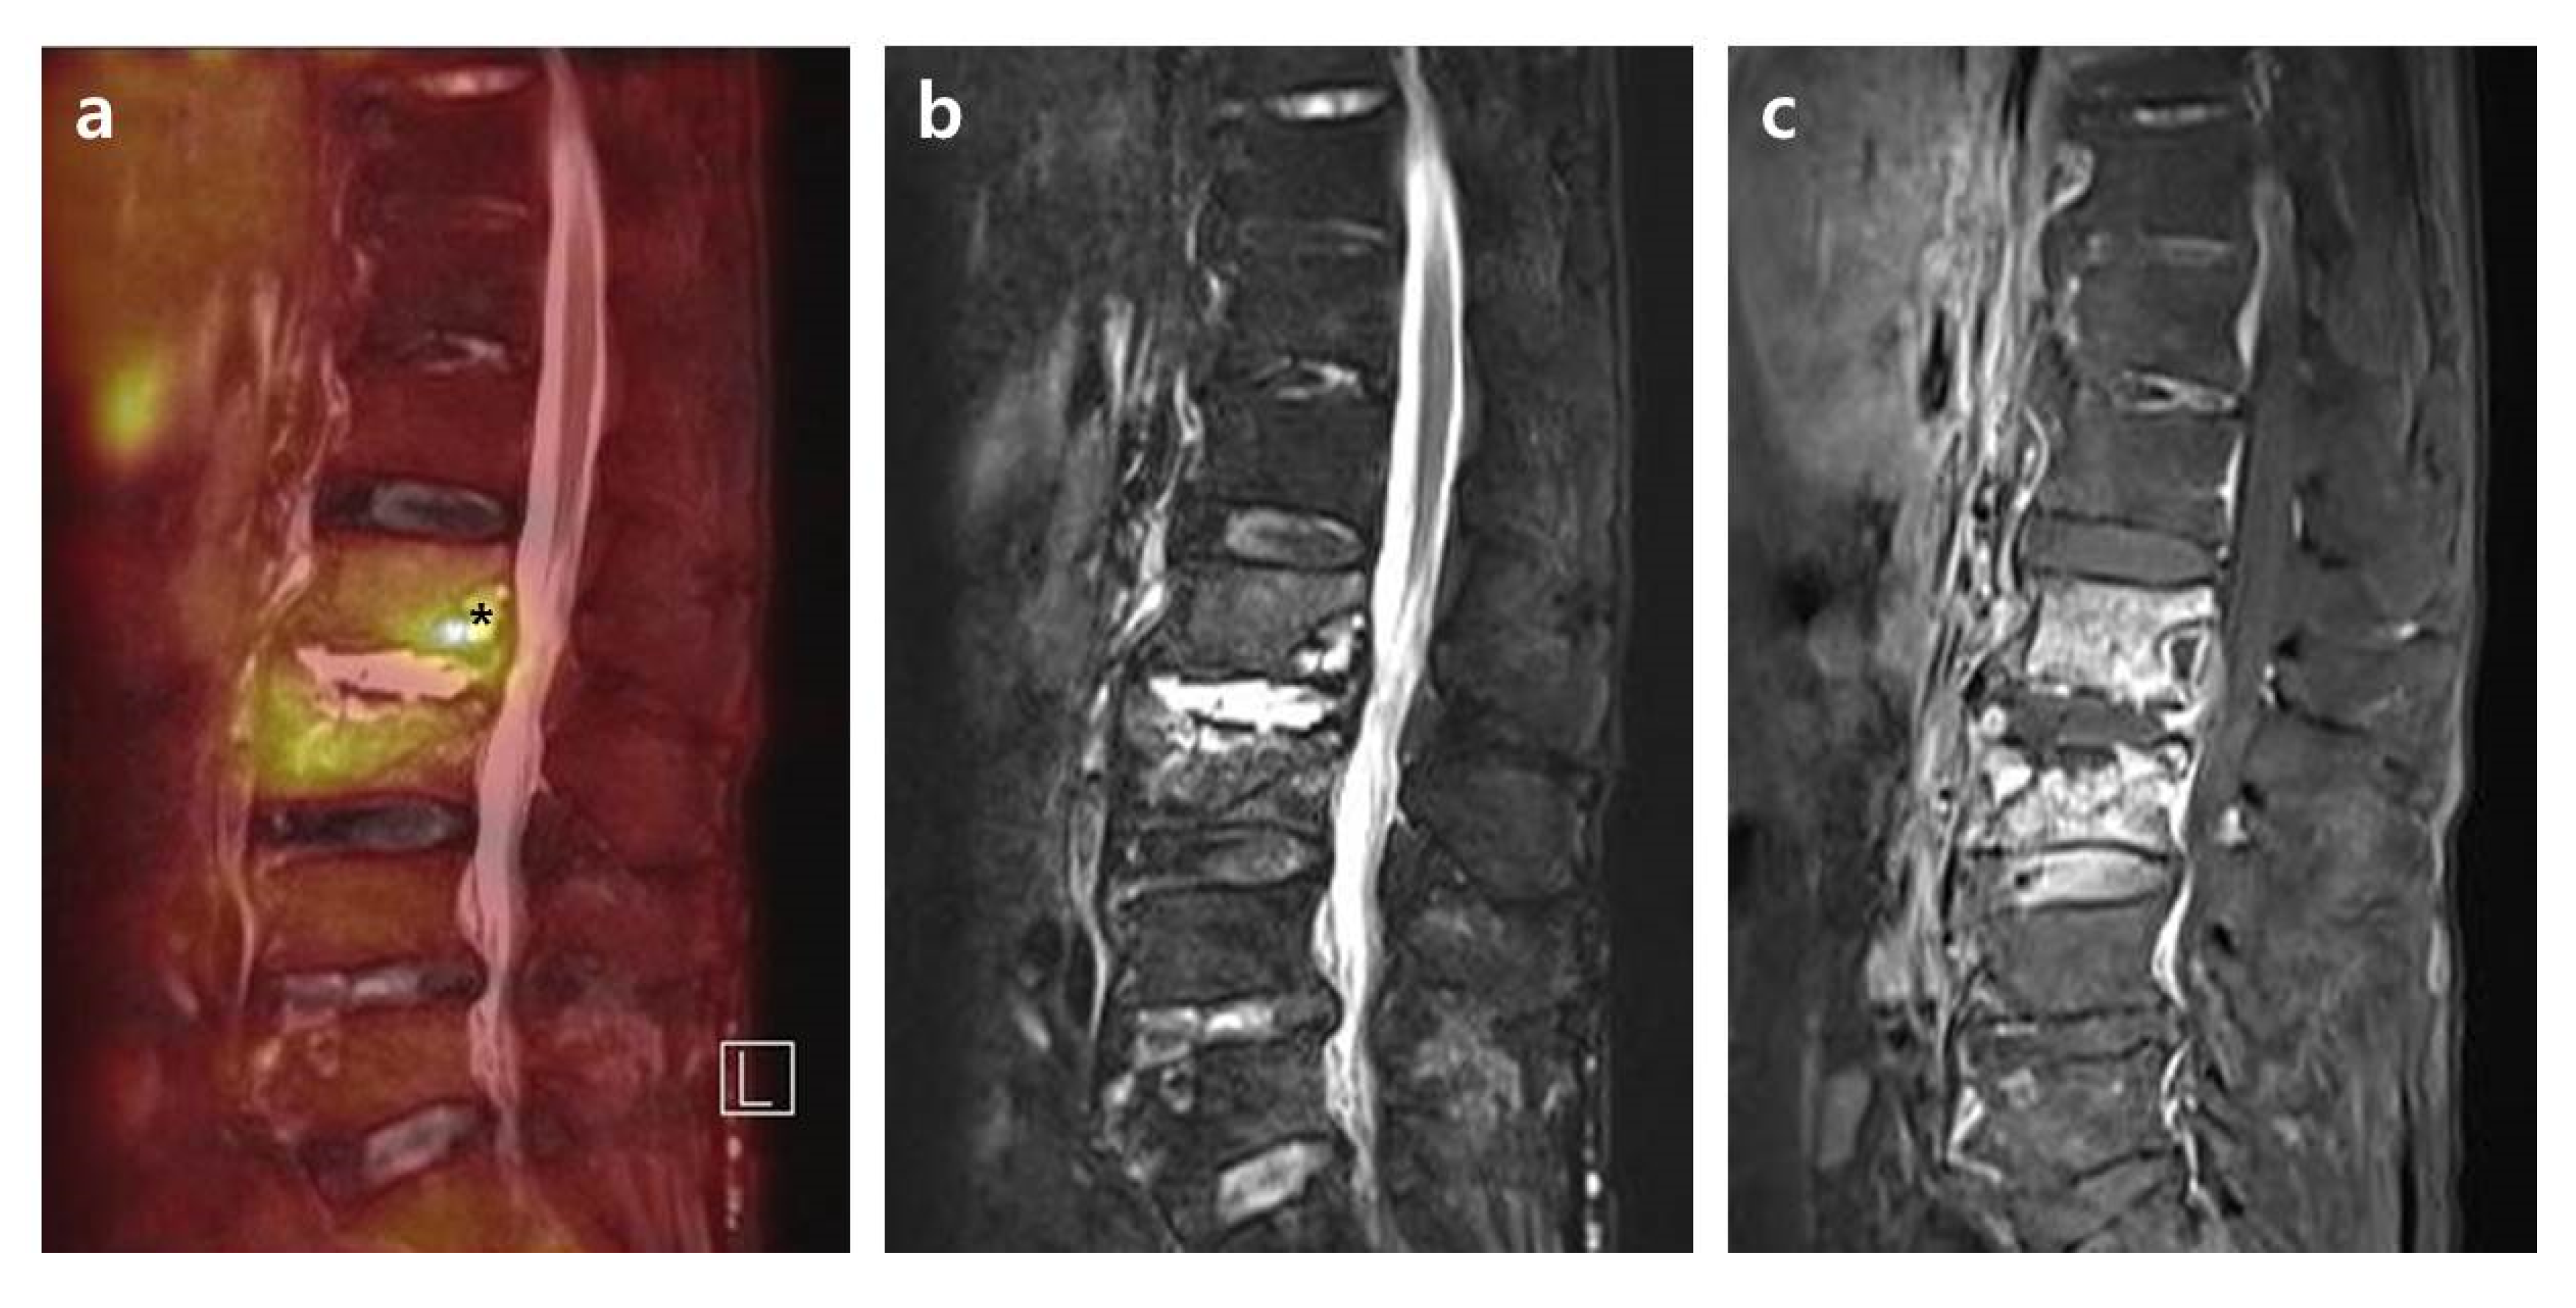

2.3.2. Distribution Patterns of FDG Uptake on FDG-PET, Contrast Enhancement on T1-Weighted Contrast MRI, and High Signal on T2-Weighted Fat Saturation MRI in PVO Lesion

- Grade I: Activities on the bone, soft tissue, and epidural space with intensity lower than or comparable to the reference.

- Grade II: Limited activities on the margin or bulk of a destroyed disc and endplates rather than the bone, soft tissue, and epidural space with overall higher intensity than the reference.

- Grade III: Significantly increased activities on overall bone and soft tissue than the reference.